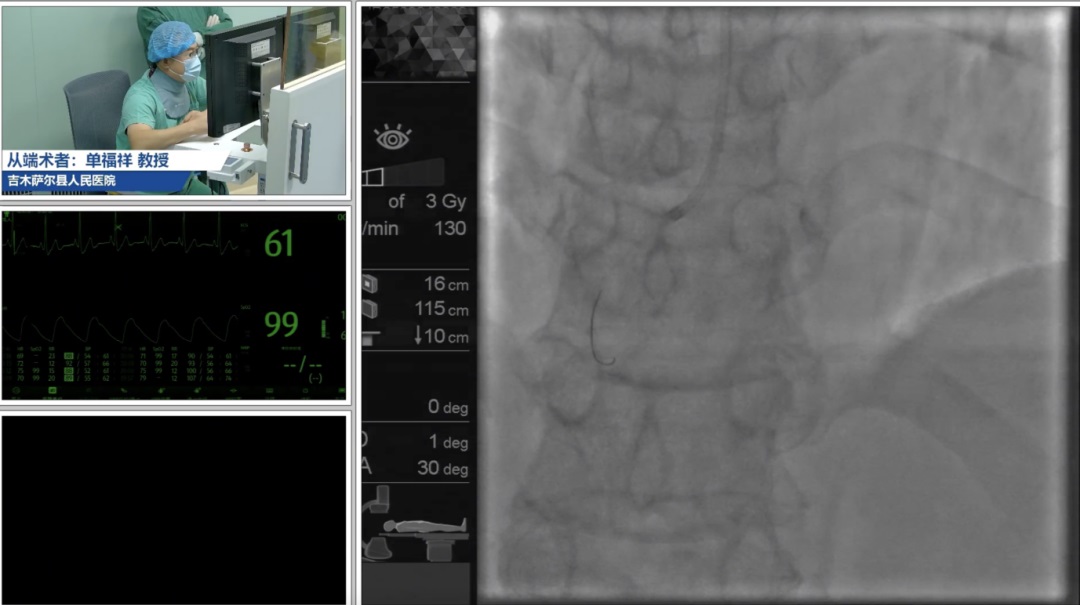

新疆维吾尔自治区人民医院杨毅宁教授、吉木萨尔县人民医院解玉涛教授以致辞开篇,介绍5G远程冠脉介入机器人手术平台的应用现状。随后,新疆维吾尔自治区人民医院杨毅宁教授、王钊教授,吉木萨尔县人民医院单福祥教授,新疆维吾尔自治区人民医院余小林教授和知脉(上海)机器人林蕾博士分别从前沿进展、临床应用、临床策略和实操技巧、项目进展、以及研发和技术保障等方面介绍了该技术的前沿进展和现状,通过手术演示,术中同步讲解,术后案例讨论,学员结合自身临床经验提出疑问,专家团队针对临床策略、应用经验等内容逐一解答。培训过程中,学员结合讲解进行了模拟操作,进一步了解该技术的操作细节。